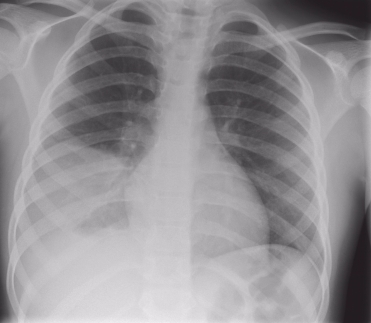

ДИАГНОСТИКА

При постановке диагноза учитывается эпидемиологическая обстановка, жалобы больного, клиническая картина заболевания, данные лабораторного и инструментального исследований. Проводится исследование крови, мочи, ЭКГ, рентген легких, кровь на серологию (обнаружение антител к легионеллам), иммуноферментный анализ, реакция иммунофлюоресценции, УЗИ брюшной полости.

Медицинские процедуры, проводимые при заболевании болезнь легионеров: Биохимический анализ крови, Клинический анализ крови, Анализ мочи, ЭКГ, Рентген, Реакция иммунофлюоресценции (РИФ), Иммуноферментный анализ, Серология, УЗИ брюшной полости